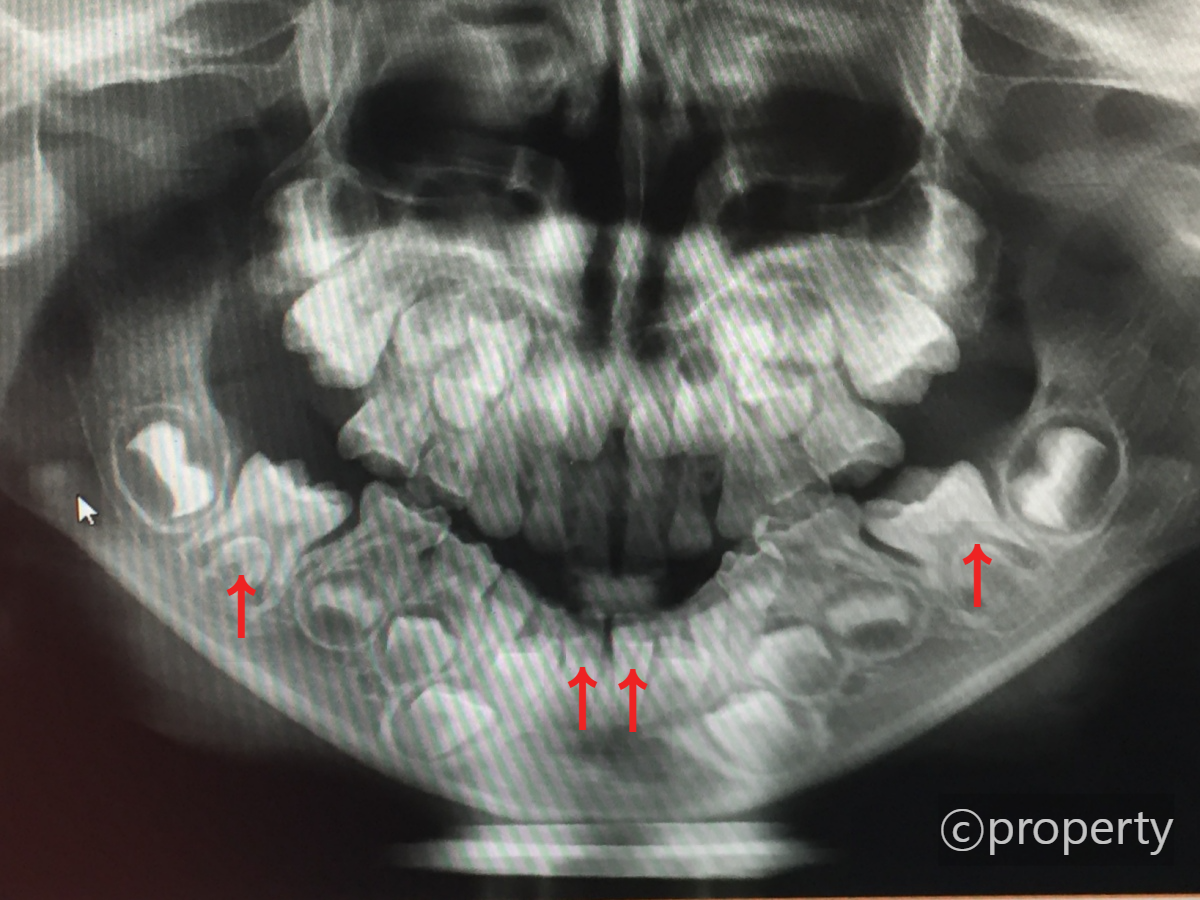

치과에서 파노라마 사진을 찍어보니 영구치 씨앗이 많이 생겨있었다. 자세히 보면 빨간색 화살표로 표시된 치아 4개는 영구치 씨앗이 없는 것을 알 수 있다.

이렇게 4개의 치아가 제일 처음 나오는 영구치인 것이다. 꼭 기억하자. 아래 앞니가 나올 때 아래 어금니도 같이 나온다는 것을!